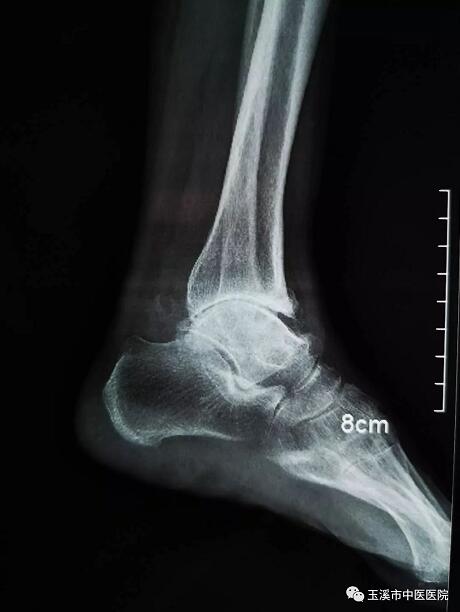

在醫(yī)務(wù)人員緊張的情況下,骨傷Ⅰ科克服種種困難,先后派出3名一線醫(yī)務(wù)人員赴千里之外的德欽縣人民醫(yī)院進(jìn)行對口援助。朱金富醫(yī)生是今年8月份去到藏區(qū)的,一到那里便積極投入工作。一位五十六歲藏族阿媽來到醫(yī)院看病時(shí),左踝關(guān)節(jié)疼痛、畸形三十余年了。 朱醫(yī)生將她收治入院,在相關(guān)檢查后,為她做了左踝關(guān)節(jié)融合術(shù)。術(shù)后藏族阿媽左踝關(guān)節(jié)功能明顯改善,生活及勞動(dòng)能力有所恢復(fù),一家人皆大歡喜。

術(shù)前X光片(左踝關(guān)節(jié)側(cè)位)